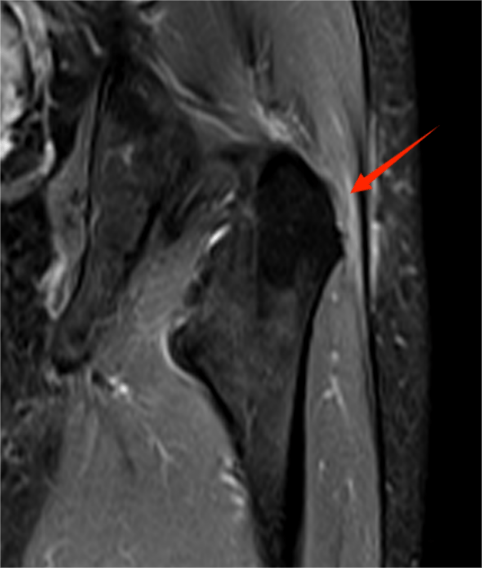

△ 打羽毛球之后的关节盂唇撕裂,周围间隙渗出